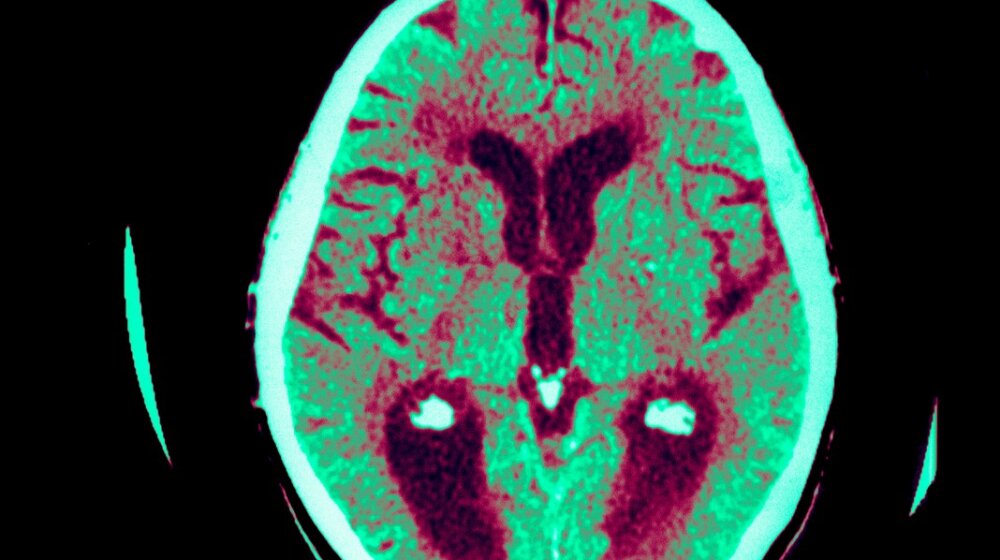

Alchajmerova bolest, foto: SGO / BSIP / Profimedia

Alchajmerova bolest, foto: SGO / BSIP / ProfimediaAlchajmerova bolest više neće biti bauk. Japanski naučnici razvili su revolucionarnu vakcinu i upravo je ona potencijalno sposobna da spreči ili modifikuje tok Alchajmerove bolesti, piše neurosciencenews.com.